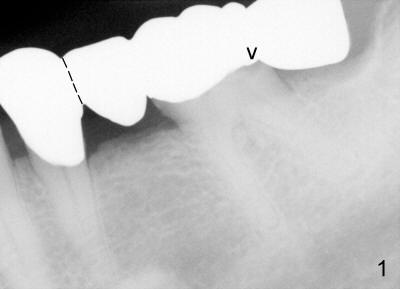

A 60-year-old man presented to clinic 2 years ago with chief complaint "bottom left bridge is loose". Dental history revealed that some of his missing teeth is due to RCT failure. Exam showed that #30 and 31 were missing. There is a 4-unit cantilever fixed partial denture (FPD) involving #18 to 21 (Fig.1); the distal margin of #19 was open (arrowhead) . Clinically, the gingiva between #18 and 19 was erythematous and edematous. The tooth #19 had mild percussion. Higher magnification of #19 showed increased periodontal ligament in the mesial and distal apices (red arrowheads in Fig.2). After sectioning between #20 and 21 pontic/retainer, as shown by dashed line in Fig.1, the distal portion of FPD came off by itself. The DOL caries under #19 retainer was confirmed. The pulp was not exposed after carious removal. Pulpal test appears to show that the tooth was vital. Temporary restoration was placed. The patient returned to clinic for #19 RCT due to tooth sensitivity 4 months later.